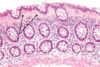

What is shown in each image?

Left: normal mucosa with villi

Right: atrophic mucosa without villi, d/t celiac disease